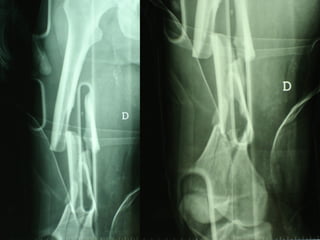

Dal Gennaio 2000 al Dicembre 2005 27 placche LISS di femore

Stabilità tramite attrito placca    osso

Osso porotico Stabilità con viti autobloccate

LISS  NCB

NCB

Conclusioni Riduzione  anatomica Minimo trauma chirurgico Corretto equilibrio fra elasticità e stabilità Precoce mobilizzazione